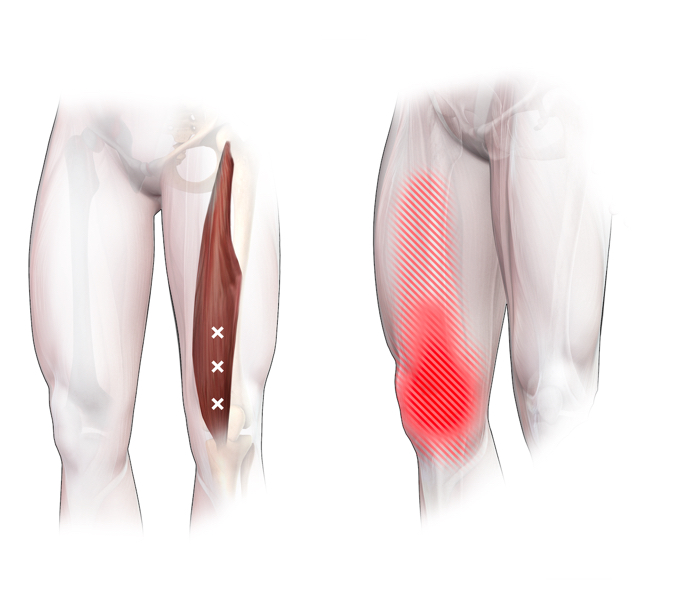

Spieren (Nederlands)

Spieren (nederlands)

Spieren (Latijn)

Spieren (latijn)